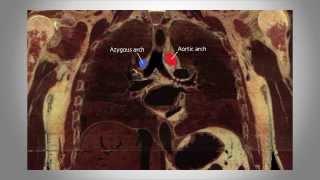

Chest Radiology - Part 1, the Basics of the mediastinum & central structures